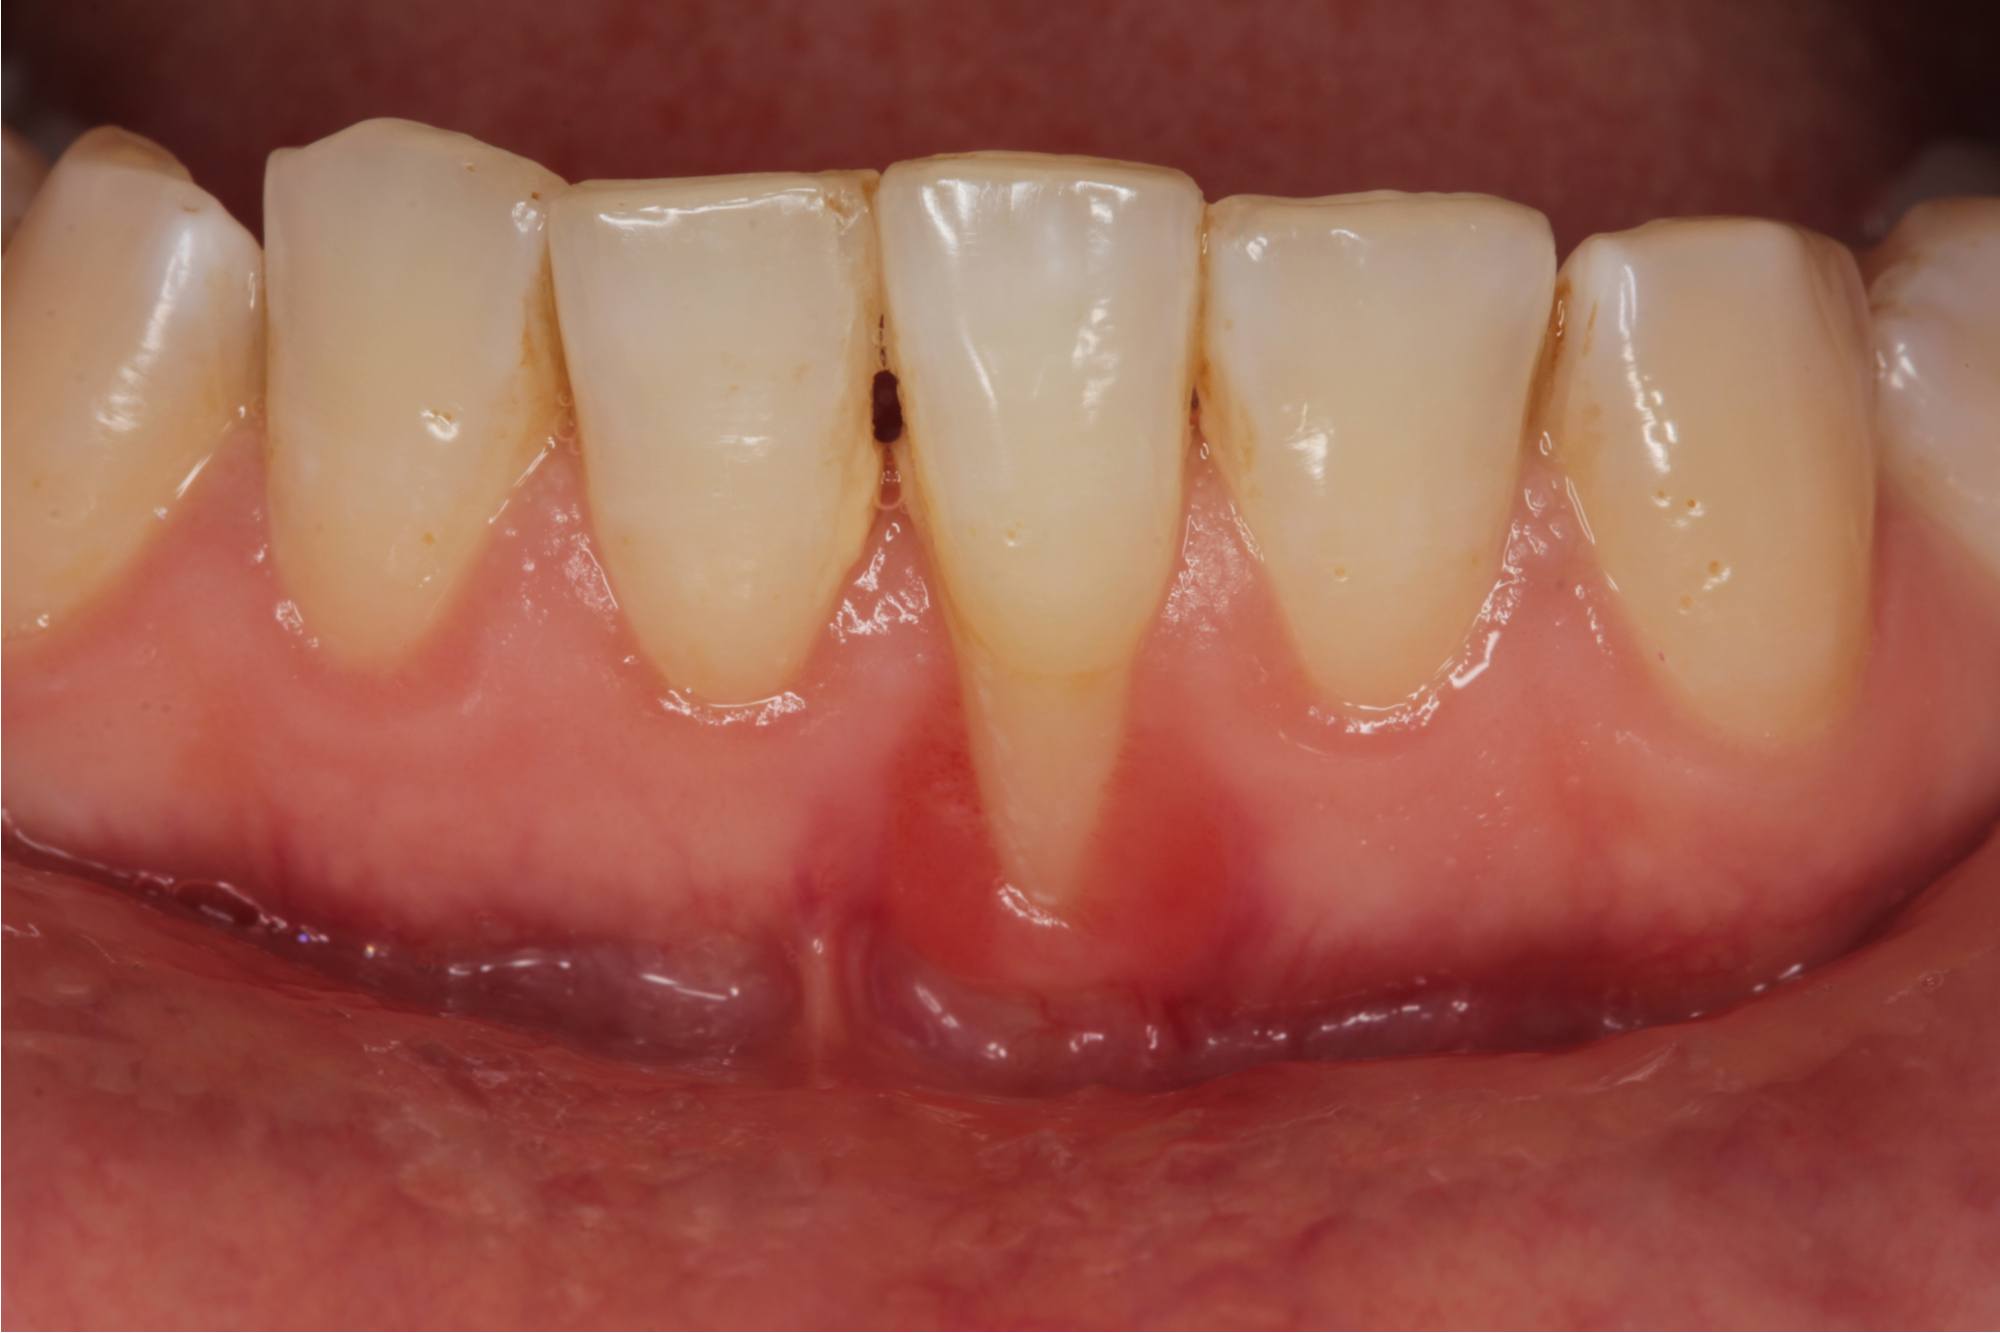

مدار الساعة -يحدث تراجع اللثة أو انحسارها لعدة أسباب، منها الالتهابات، وتنظيف الأسنان بفرشاة غير مناسبة، وصرير الأسنان، والشيخوخة، والتدخين، والإصابات. ويؤدي انحسارها إلى كشف الجذور في الأسفل.

كما تسبب عوامل أخرى انحسار اللثة، مثل التغيرات الهرمونية التي تصاحب الحمل، ومرض السكري، والحشوات التالفة، والجسور التي لم تعد مناسبة، والاستخدام طويل الأمد لأدوية تسبب الجفاف.وإجابة على سؤال: هل يمكن أن تنمو اللثة مرة أخرى؟ لا يمكن أن تنمو اللثة بشكل طبيعي. ومع ذلك، يمكن الوقاية من مزيد من تراجع اللثة، ويمكن للجراحة استعادة بعض الأنسجة.ويعتمد علاج انحسار اللثة على السبب الكامن وراء ذلك، والذي قد يتطلب أو لا يتطلب جراحة.وتعتبر العناية الجيدة بالتنظيف بالفرشاة، وحضور مواعيد تنظيف الأسنان لدى الطبيب بانتظام، من العوامل التي توقف انحسار اللثة.ويمكنك استشارة الطبيب بخصوص زاوية التنظيف بالفرشاة المناسبة، وأيضاً إمكانية استخدام الواقي المناسب للأسنان أثناء النوم لمنع الضغط عليها.ويعد التقشير وكشط الجذر من أولى العلاجات لانحسار اللثة التي قد يوصي بها طبيب الأسنان. تزيل هذه الإجراءات الجير والبلاك من تحت خط اللثة، حيث لا يمكن للفرشاة المنتظمة الوصول إليها. بعد ذلك، سيستخدم طبيب الأسنان أدوات خاصة لتنعيم الجذور، مما يساعد اللثة على الالتصاق بالسن.وبالنسبة لحالات الانحسار الشديد قد يقترح طبيب الأسنان إجراء جراحة يأخذ فيها قطعة صغيرة من أنسجة اللثة من مكان آخر في الفم ويستخدمها لتغطية جذور الأسنان المكشوفة.وتوجد أيضاً تقنية جراحة الثقب، وهي علاج جديد لانحسار اللثة الخفيف إلى المتوسط. وهو إجراء طفيف التوغل يتضمن إحداث ثقب صغير في أنسجة اللثة فوق جذر السن المكشوف. ويقوم الطبيب بإدخال أداة في الحفرة لفصل اللثة عن السن، ثم تمديد اللثة وإعادة وضعها فوق جذر السن المكشوف.هل تنمو اللثة مرة أخرى بعد انحسارها؟